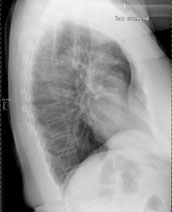

Eine 69-jährige Patientin klagt über einen seit mehr als 4 Wochen anhaltenden Husten mit wenig Auswurf. Die Frage nach Dyspnoe wird verneint. Fieber besteht keines.

Die körperliche Untersuchung ist unergiebig. Der behandelnde Arzt hat aufgrund der Raucheranamnese und des nicht enden wollenden Hustens ein Röntgenbild gemacht:

Thorax seitlich

Bild vergrössern

Welche Befunde fallen auf (mehrere richtige Antworten möglich)?

Wie beurteilen Sie nun das Röntgenbild?